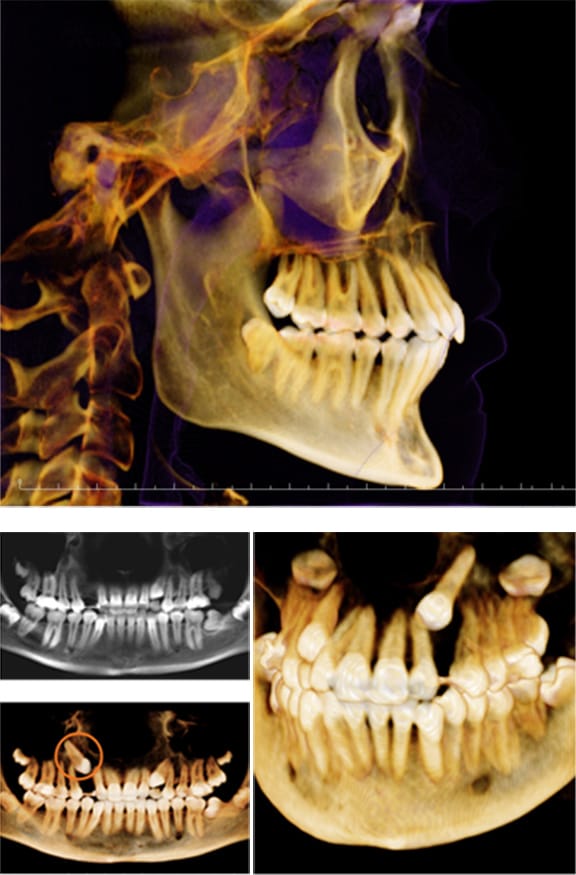

Cone Beam Computed Tomography

To keep your radiation dose to a minimum, our staff uses a Cone Beam Computerized Tomography (CBCT) machine that has one of the lowest radiation doses in the industry. Although not every person needs a CT scan, when it is necessary to take one, you can rest assured you are receiving the lowest dose possible. At the same time the images have extremely high resolution and allow our dentists to properly diagnose your oral condition.

Some of the most common procedures in which the CBCT is used are:

- Impacted teeth

- Locating oral pain

- Evaluating jaws, nerves, nasal cavity, and sinuses

- Reconstructive surgery

- Implant placement

- Diagnosing TMJ